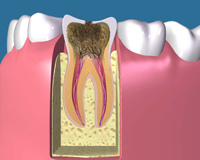

C3 虫歯の後期です。神経まで虫歯が進行しているので神経を取 る治療をし、歯の根の中を綺麗にしなければなりません。 今までの虫歯の状態に比べて治療の回数が増えます。 |

C4 ほとんど歯(歯冠)の部分は残っていません。 歯の根の先に膿が出来てしまうことがあります。 根幹治療をして治る場合もありますが、治らない場合は歯を 抜かなければならないこともあります |

虫歯などによって歯の神経に細菌が入り込んで炎症を起こすと、歯の神経は死んでしまいます。

深い虫歯などが原因で神経を取ったあと、根の中の中空部分をきれいにして処置をすることを根管治療と言います。

虫歯菌に冒されている部分をすべて削り取ります。

根管内を洗浄し、根管の長さを測ります。

根管内に菌が残らないようにするため、丁寧に消毒を行います。

根管内のすみずみまで薬剤を充填し、隙間ができないように密封します。